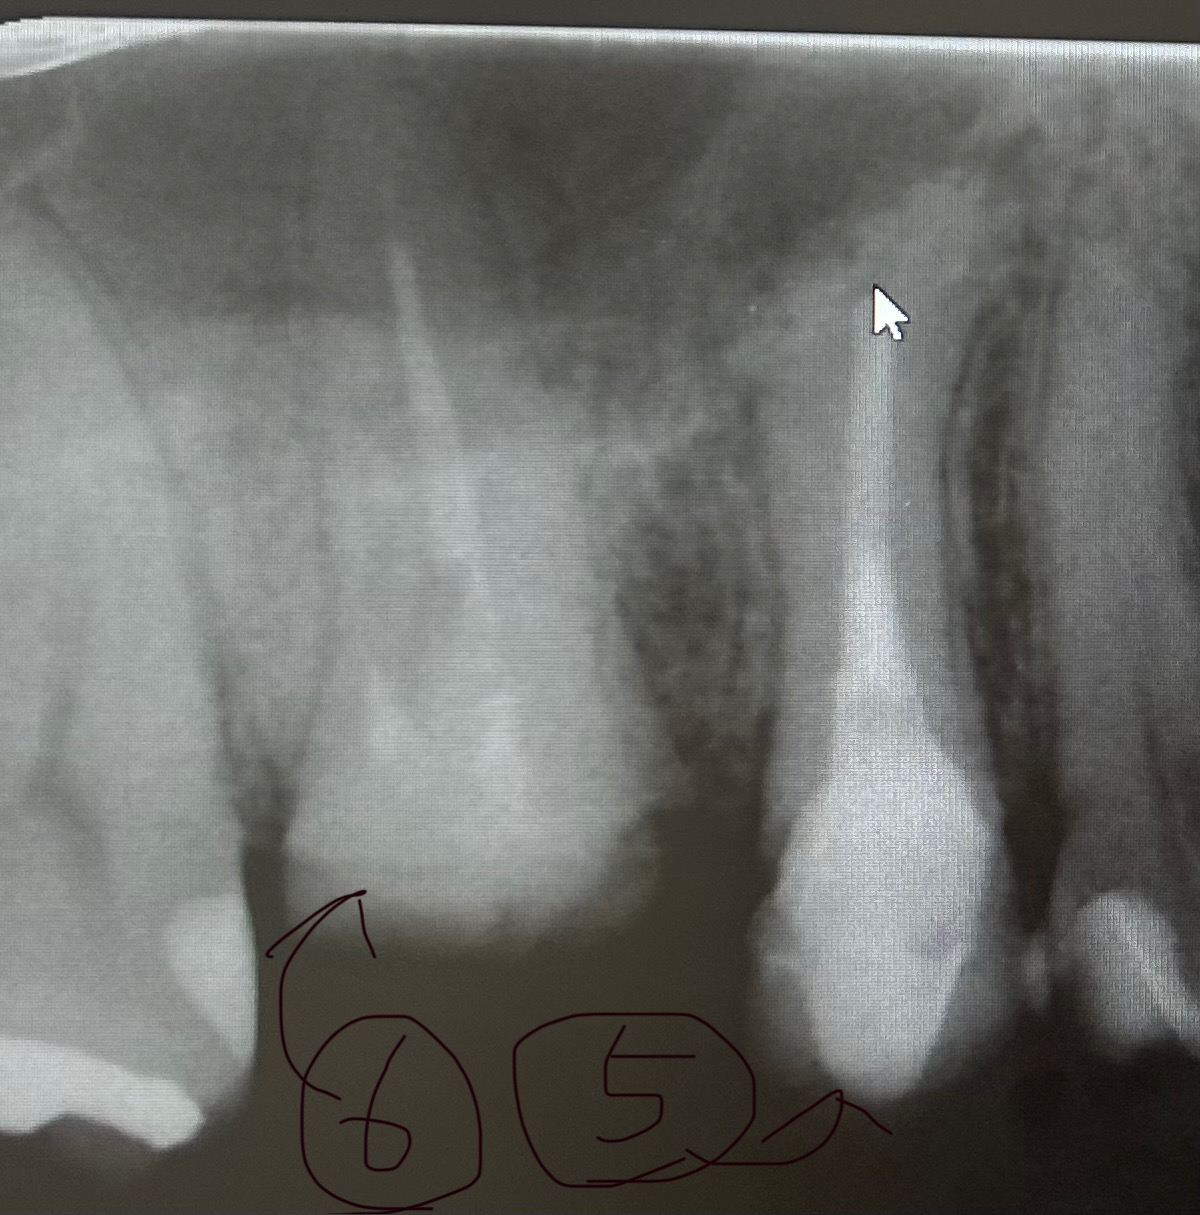

大学病院の、歯科に紹介されて小さいレントゲンにて、5番は下までちゃんと薬も入ってるし大丈夫でしょう。

と言われましたが、歯の先がモヤモヤしているところがあり、気になります。

私としては、もう、この5番の歯(矢印の方)は、抜歯すべきなのかと思ったのですが、どう思われますか。

画像1